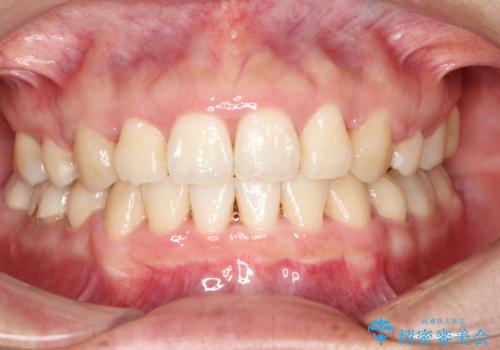

上下の歯のガタガタ ワイヤーでの抜歯矯正で整った歯並びへ

- 上下の歯のガタガタを治したいとのことで来院されました。

がたつきの度合いが強いのと、口元をなるべく引っ込めたい希望がありましたので、ワイヤーでの抜歯矯正となりました。

ガタガタが重度の方は抜歯が必要となることが多いです。

抜歯スペースを使って前歯を引っ込めることにより、口元の突出感も改善できました。